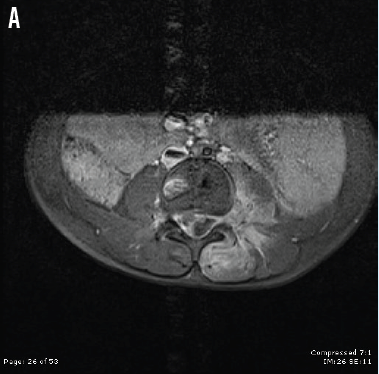

Sheena Tonkin, MD; Kyrie Shomaker, MD

A 5-year-old previously well boy was referred to the emergency department after a week of intermittent fever along with progressive left back and leg pain and refusal to bear weight.